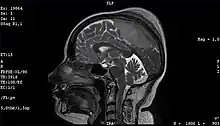

| A human skull showing hyperostosis | |

Meningioma of the middle third of the sagittal sinus with large hyperostosis